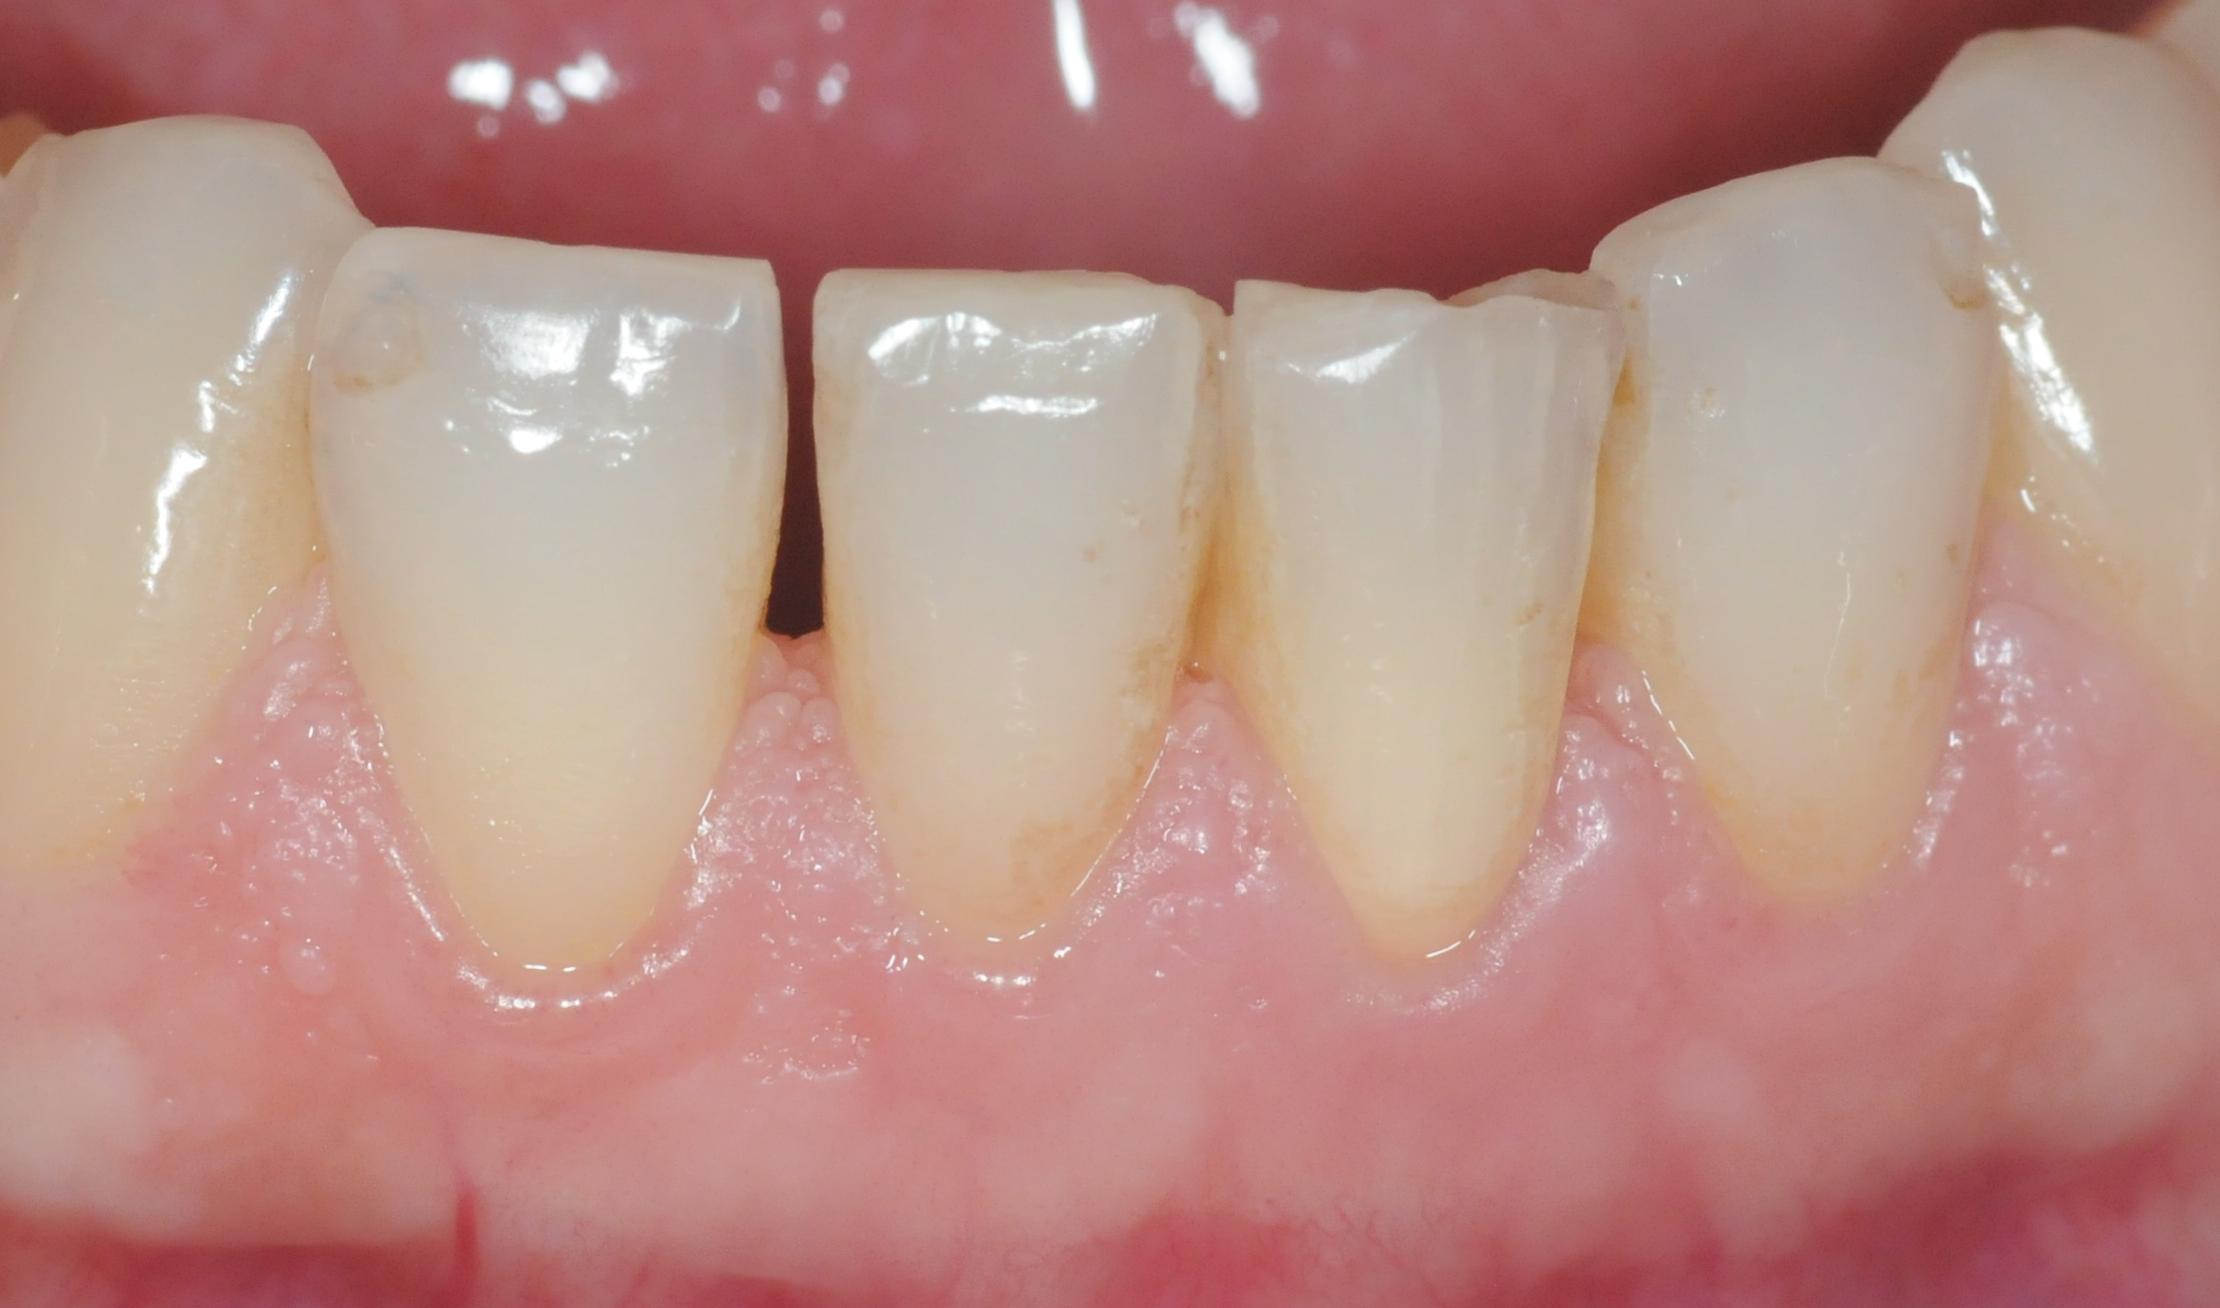

Zustand nach einer Woche Bleicheinlage. Der Zahn kann nun mit einer definitiven Füllung versorgt werden.

Es wird auch oft gefragt, wie lange denn der Bleicheffekt anhält. Beim Bleichen werden Farbstoffe, die sich in den Zahn eingelagert haben optisch inaktiviert. Danach sollten eigentlich keine weiteren Farbstoffe mehr da sein, somit sollte das Bleichergebnis dauerhaft sein. Wir haben mittlerweile Langzeitergebnisse von über 17 Jahren. Das Ergebnis hat sich nicht verändert.

Hier ist aber auch deutlich zu sehen, was Internes Bleichen (Bleaching) nicht kann: vorhandene Füllungen bleiben wie sie sind und kommen durchs Bleichen stärker zur Geltung. Diese müssen dann gegebenenfalls getauscht werden, um die Farbe an den gebleichten Zahn anzupassen. Das gleiche gilt für Verfärbungen als Auflagerungen auf dem Zahn, diese werden im Rahmen der Zahnreinigung wegpoliert.